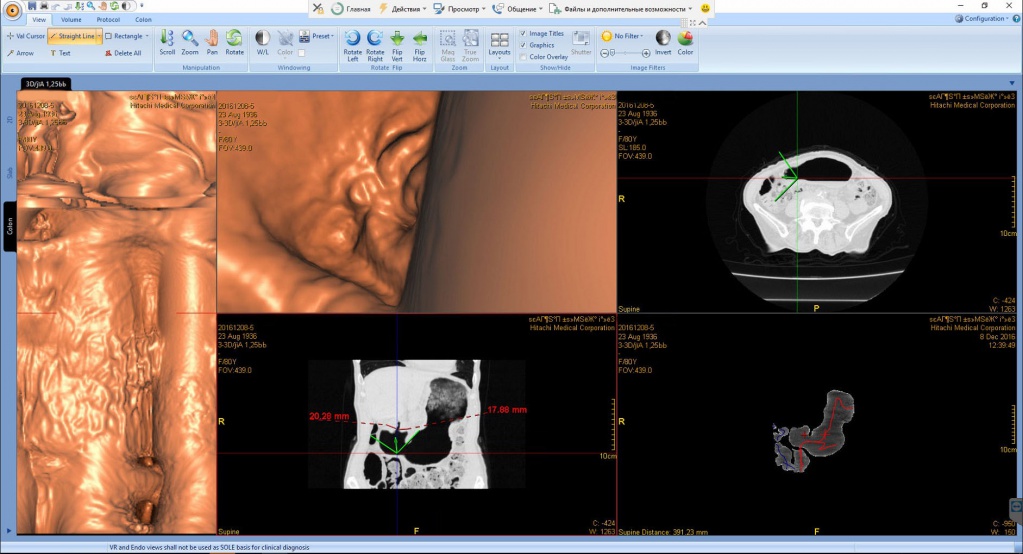

Рак ободочной кишки в зоне селезёночного угла с прорастанием опухоли в переднюю стенку желудка

Патология с точки зрения диагностики так и клиники интересна тем, что диагностировать удалось в полном объёме только на КТ, при проведении виртуальной колоноскопии. 3D реконструкция и в этом случае, как нельзя кстати. Пациент удачно прооперирован, с восстановлением физиологии пищеварительной трубки с относительно благоприятным клиническим исходом. Через год после комбинированного лечения отдалённых метастазов не выявлено.